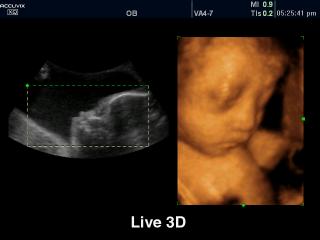

Fetus, Live 3D

Accuvix-XQ. Fetus, Live 3D.